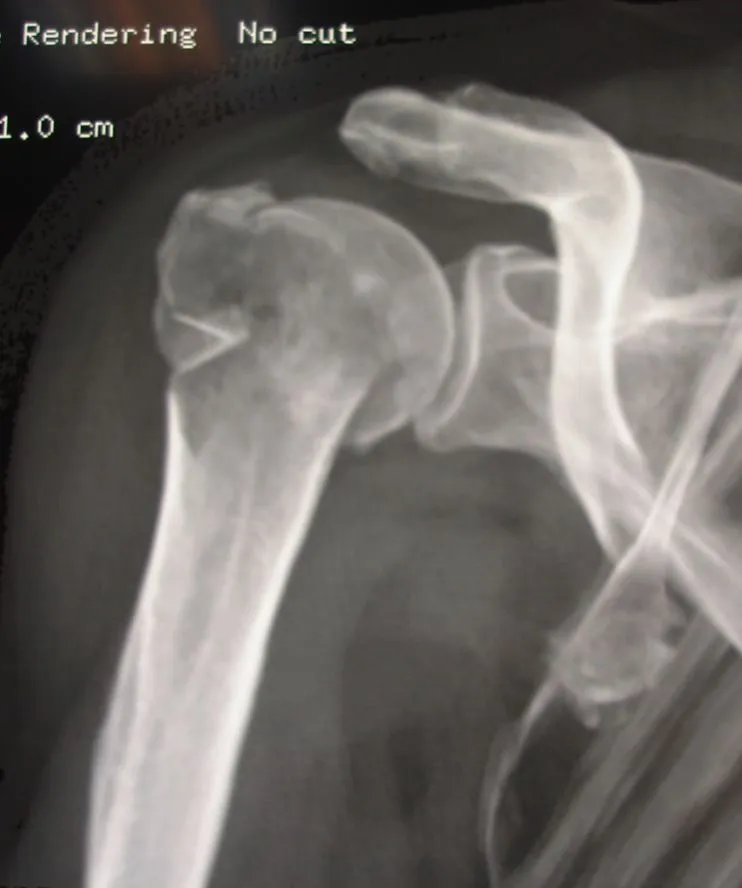

fracture neer 4

enclouage fracture 4 fragments épaule